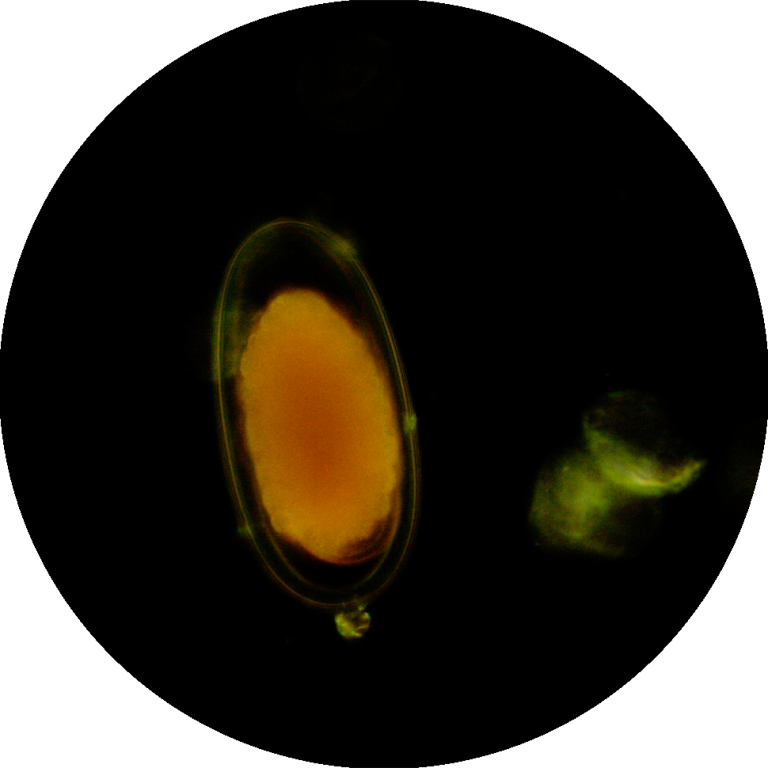

Aprofundar a Identificação Microscópica: Fornecer conhecimentos detalhados sobre a morfologia e ciclos de vida dos principais parasitas encontrados em amostras sanguíneas (ex: Babesia, Anaplasma, Dirofilaria) e fecais (ex: ovos e oocistos de nematóides, cestóides, trematóides e protozoários), utilizando as modalidades de campo claro e campo escuro.

Utilizar a Microscopia de Campo Escuro: Ensinar a aplicação da microscopia de campo escuro para a visualização de parasitas no seu estado vivo, permitindo a observação de motilidade e características que podem perder-se em preparações fixas.

A microscopia continua a ser a técnica laboratorial de eleição para o diagnóstico de infeções parasitárias, sendo as técnicas de coloração, usadas na preparação da amostra, o fator decisivo para um diagnóstico correto e eficaz.